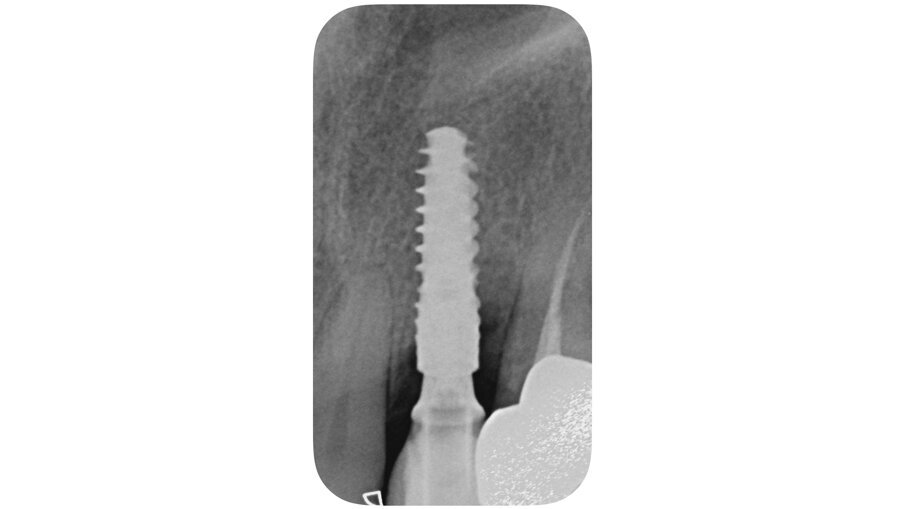

La paziente, B.G. di sesso femminile, di anni 71, è giunta alla nostra osservazione per la mobilità e lieve dolore a carico dell’elemento 2.2 (incisivo laterale superiore sinistro) (Fig. 1). All’esame ispettivo l’elemento presenta mobilità di grado 3. Al sondaggio parodontale presenta una tasca mesiale di 7 mm e di 3 mm lungo le altre superfici del dente. All’esame radiografico, eseguito con radiografia endorale periapicale, si osserva un’area di radiotrasparenza riconducibile a riassorbimento osseo soprattutto in sede mesiale (Fig. 2).

È stato inserito un impianto Straumann BLX 3.75 mm di diametro per 12 mm di lunghezza, con superficie SLActive seguendo l’asse protesico ideale (Figg. 4, 5). Avendo conseguito una stabilità primaria eccedente i 35 N/cm è stato realizzato un restauro provvisorio avvitato in composito su componente in Titanio da provvisori. Nonostante una sostanziale congruità della forma del provvisorio con la parte superficiale dell’alveolo, è stata utilizzata una matrice dermica suina (Botiss Mucoderm) allo scopo di sigillare il gap presente tra provvisorio e bordo mucoso dell’alveolo. Tale matrice, opportunamente sagomata e forata in modo da essere stabilizzata dal provvisorio stesso, è stata posizionata in modo da non rimanere esposta al cavo orale. Non sono state necessarie suture (Figg. 6-8).

Fig. 2_Radiografia periapicale in sede 2.2.

Fig. 5_Rx periapicale post-impianto.